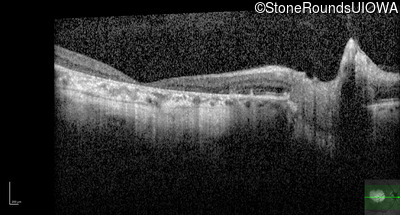

Optical Coherence Tomography - Right - 20/125

Exemplar / OCT Stack